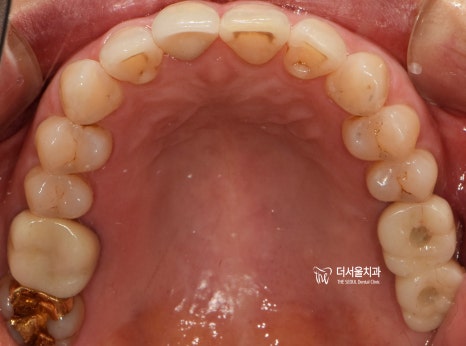

3개월 뒤,

맞춤형 지대주로 기둥을 끼워드리고

지르코니아를 연결해 드리면서

네비게이션 임플란트 수술이 끝나게 되었습니다.